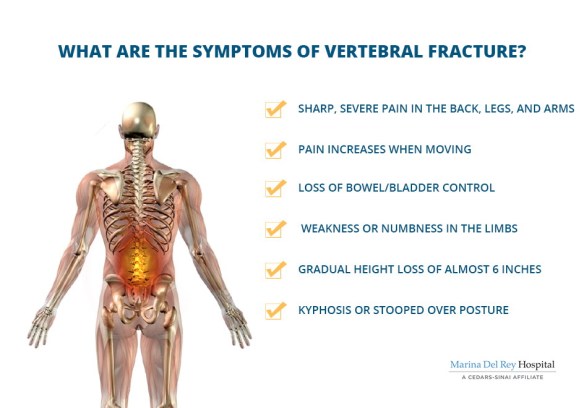

Who needs toenails anyways?1?!